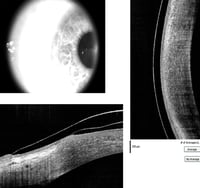

OCT has replaced more invasive diagnostic tests as the primary way of monitoring the progression of many retinal conditions and diseases and their response to treatment. OCT also provides high-resolution visualization of anterior segment structures such as the cornea and angle, and measures the thickness of the retinal nerve fiber layer to aid in the diagnosis and monitoring of glaucoma and other diseases of the optic nerve. Anterior segment

![]() |

| Anterior segment OCT of a scleral contact lens on the eye |

OCT is also used to custom design specialty contact lenses and evaluate proper fit. Originally adopted by specialists, “OCT has become an essential component of primary eye care,” says Thomas A. Wong, OD, Director of New Technologies at SUNY State College of Optometry.